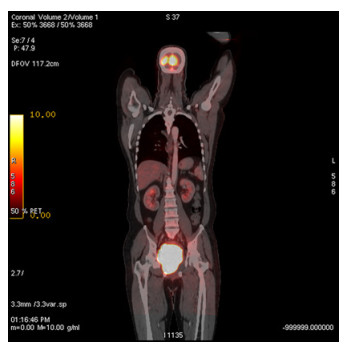

Abstract: Rectal malignancy is usually symptomatic due to its location, and most of the time presents with pain and bleeding due to its growth and ulceration. It is difficult to identify the primary as carcinoma or lymphoma based on symptoms only, as both have a similar presentation. As it presents the rarest form of histology, non-Hodgkin's lymphoma in the rectum is still difficult to diagnose initially, and its treatment is debatable. We describe the case of a 49-year-old male from Bangladesh with the same presentation. His treatment was delayed for more than a month as immunohistochemistry and staging delayed the final diagnosis. The disease was diagnosed as stage IE with the help of a positron emission tomography (PET)-CT scan, and due to the local progression the patient had a massive rectal bleeding that needed an urgent intervention. Radiotherapy was applied to stop the bleeding. Hypofraction followed by a conventional fraction of external beam radiotherapy (EBRT) with a total of 40 Gy was applied. Post-EBRT digital rectal examination showed no residual except scaring, and a PET scan was also negative for residual disease. Due to uncertainties and lack of any precious guideline, 6 cycles of adjuvant chemotherapy with the R-CHOP schedule were also completed. Without surgery, the combination of EBRT and chemotherapy helped to preserve the organ, and the patient has been disease free for more than 2.5 years since his treatment.